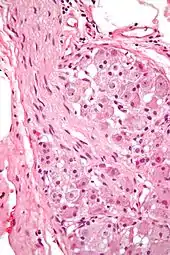

During the late 1800s, early 1900s, Spanish Neuroscientist and Pathologist Santiago Ramón y Cajal proposed Neuron theory which basically introduced the idea that the Nervous system contained cells called the Neuron. The process he used was called Golgi staining of the vertebrae retina. Cajal was able to differentiate between different types of Ganglion cell based on dendritic morphology, cell body and dendritic tree size, and number of sub layers in which they arborize/stratification layers. Through this study, he discovered that the ganglion cell distribution amongst vertebrates were pretty similar minus the Rods and cones in the retinas.[3]